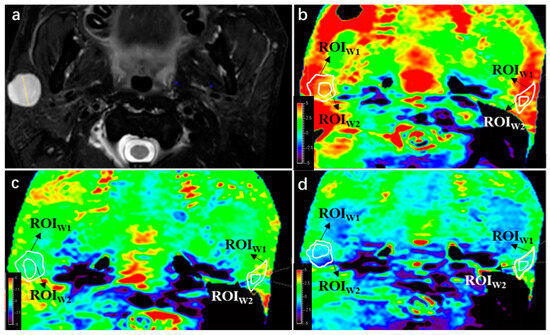

The integrity and hyperintensity artifact scores were compared between PTs and PGs for each APT sequence. Statistical significance was determined using appropriate statistical tests, and p-values are shown. No significant difference indicates p > 0.05. The results of qualitative analysis showed that there was no significant difference in integrity between PTs and PGs in APT 1 and APT 2 (p = 0.082 and 0.723, respectively), while PGs had better integrity than PTs in APT 3 (p < 0.05). After excluding PTs and PGs with integrity score = 1, the hyperintensity artifact analysis revealed that PTs had better image quality of hyperintensity compared to PGs in APT sequences 2 and 3 (p < 0.05), while there was no significant difference in APT sequence 1 (p = 0.669). Further details and a case example can be seen in Table 5 and Figure 3, respectively.

The results of the comparison among the three APTw sequences (APT1, APT2, and APT3) showed that PTs had better integrity in APT 1 compared to APT 2, and APT 2 had better integrity compared to APT 3. However, there was no significant difference in integrity between the three sequences for PGs. In terms of hyperintensity artifacts, lesions in both APT 2 and APT3 had less hyperintensity artifacts compared to APT1 (p < 0.05), while there was no significant difference in hyperintensity artifacts between APT 2 and APT 3 for PTs (p = 0.157). Similarly, PTs in APT 2 and APT 3 also had less hyperintensity artifacts compared to APT 1 (p < 0.05), and there was no significant difference between APT 2 and APT 3 (p = 0.083). Further details can be seen in Table 6.

Figure 3. APTw image quality change with B1 power change. (a) A lesion was found at right side of parotid gland in this 42-year-old male on T2WI, a pathologically proven pleomorphic adenoma. (b) APTw image with B1 = 2 μT; integrity scores of the lesion and parotid gland were both 4, while hyperintensity artifact scores were 3 and 2, respectively. (c) APTw image with B1 = 1 μT; integrity scores of the lesion and parotid gland were both 4, respectively, while hyperintensity artifact scores were both 4. (d) APTw image with B1 = 0.7 μT; integrity scores of the lesion and parotid gland were 3 and 4, respectively, while hyperintensity artifact scores were both 4.